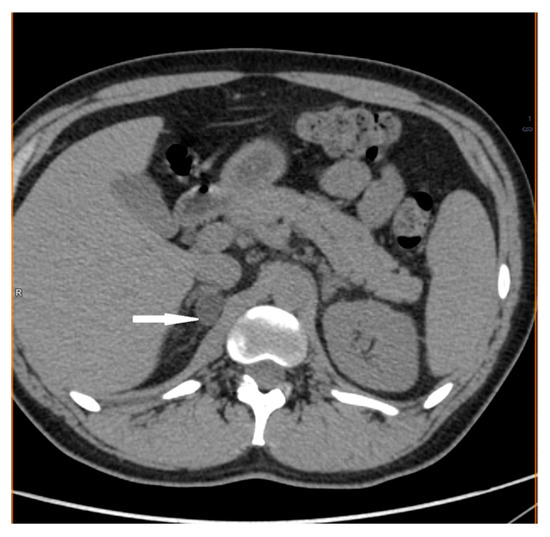

2.1. Case 1